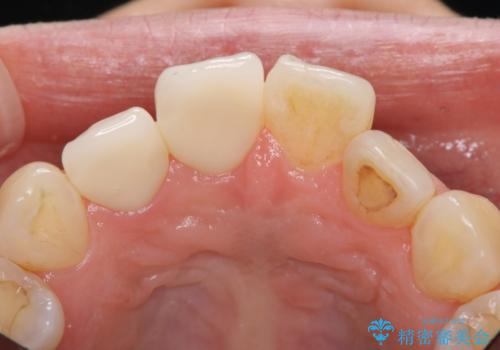

- 昔治療したプラスチックの材料が目立つから、セラミックで被せたいということを主訴で来院された患者様です。

虫歯治療をし、仮歯を制作し、オールセラミック(スタンダード)にて治療させていただきました。

オールセラミッククラウン(スタンダード)2本 20万円 税別